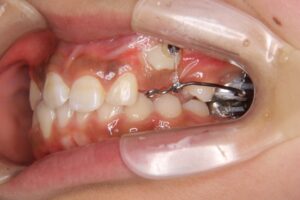

● 牽引治療の流れ

-

口腔外科で歯ぐきを切開し、埋伏歯の一部を露出させる

露出した埋伏歯に小さな装置(ボタン)を付ける

矯正装置のワイヤーとゴムの力でゆっくり口腔内へ引き出す

牽引には数ヶ月〜1年以上かかることもあり、治療全体の期間に影響します。

● 痛みについて

牽引はゆっくり弱い力で進めるため、通常の矯正と同じ程度の違和感で済むことが多いです。